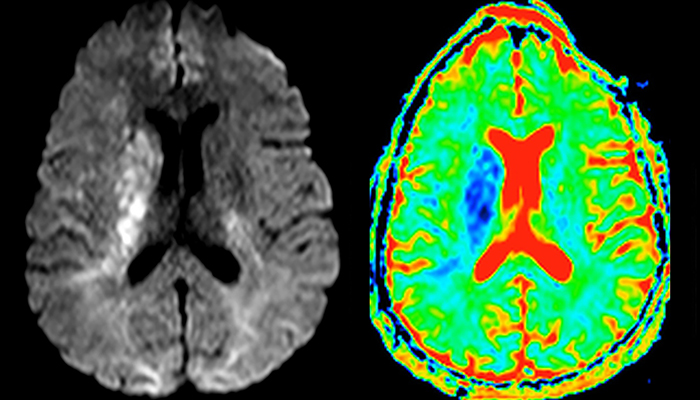

The first challenge in MRI of stroke is speed. The patient typically arrives from an ambulance in the MRI preparation room and the installation is done on a separate dock outside the scanner room. “The venous access is placed during the neurological examination. If the delay from the first symptoms allows the patient to receive thrombolysis we do a very fast examination that typically lasts about 11 minutes including the pre-scans. In the case of transient ischemic stroke we usually add ASL perfusion because in some symptoms with negative diffusion, ASL sometimes indicates a vascular origin.”

“Every center is different, but for me the ideal protocol for stroke includes diffusion weighted imaging, FLAIR, and fast susceptibility imaging,” says Dr. Savatovsky. “Our fast susceptibility weighted imaging takes 50 seconds, so it’s as fast as T2*-weighted imaging. It visualizes hemorrhage but also the clots. We also do 3D MR angiography that provides information on cervical and brain vessels. If the patient does not need immediate treatment, or if additional information is needed to decide on treatment, we might also add perfusion imaging and post-contrast T1-weighted imaging.”